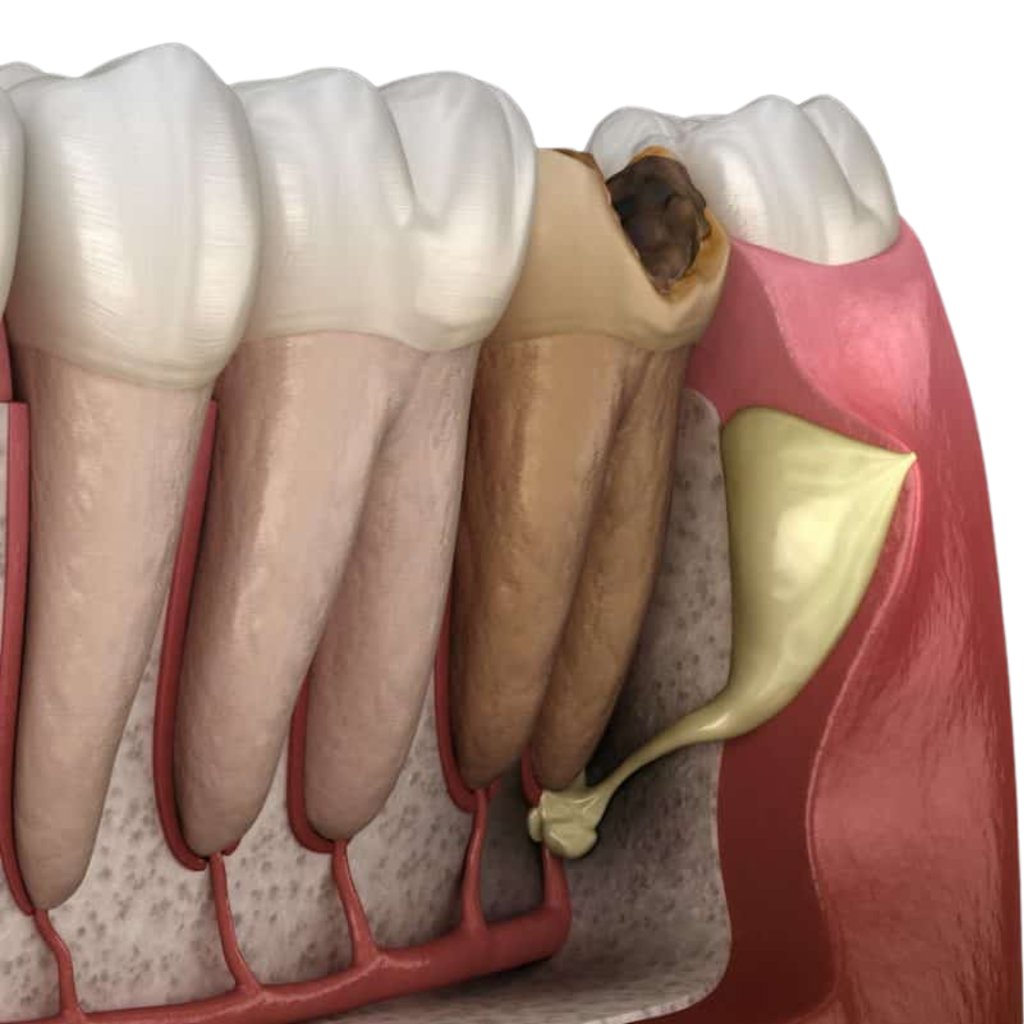

¿Cuándo se necesita una Endodoncia?

Se necesita cuando la pulpa del diente (el tejido interno del diente) se inflama o se infecta debido a caries, una lesión o una fractura.

Cirugía para eliminar infecciones en la punta de la raíz y preservar el diente.

Apicectomías